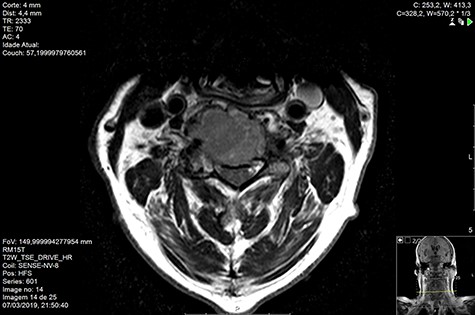

Computed tomography (CT) (Figs 1–3) and magnetic resonance imaging (MRI) (Figs 4–6) of the cervical spine were performed and revealed a lytic lesion involving most of C4, C5 and C6 vertebral bodies with bilateral extension to the posterior spinal elements of C4 and C5 and complete disruption of C4-C5 and C5-C6 intervertebral discs.

The Spinal Instability Neoplastic Score (SINS) [4, 6, 7] for assessing spinal instability from metastatic disease was used and the lesion was deemed unstable (SINS 13), with impending risk of increased neurological damage.

MRI and CT scans performed at 90 days post-radiation therapy showed an arrest of further progression of instability and resolution of the lytic lesion (Figs 7–13).